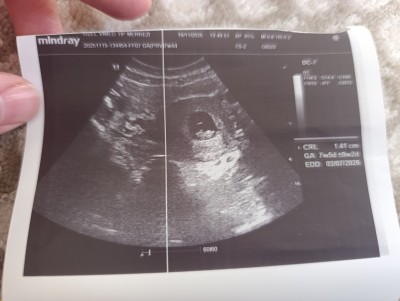

Kızlar 7+5 tahmin yapabilir misiniz ? Meraktan soruyorum

Gebelik haftası 7+5